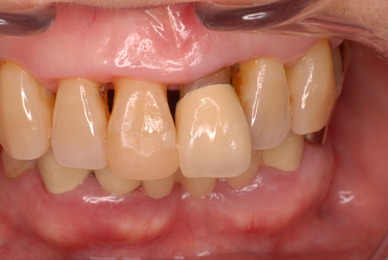

お口の中から差し歯、入れ歯、詰め物を追放しましょう!

口の中の病気を治し、病気を興さない医療を目指します。

二度とお口の中へ変なものを入れなくても済むように

予防に精進いたしましょう!安全な矯正、美容を目指しましょう!